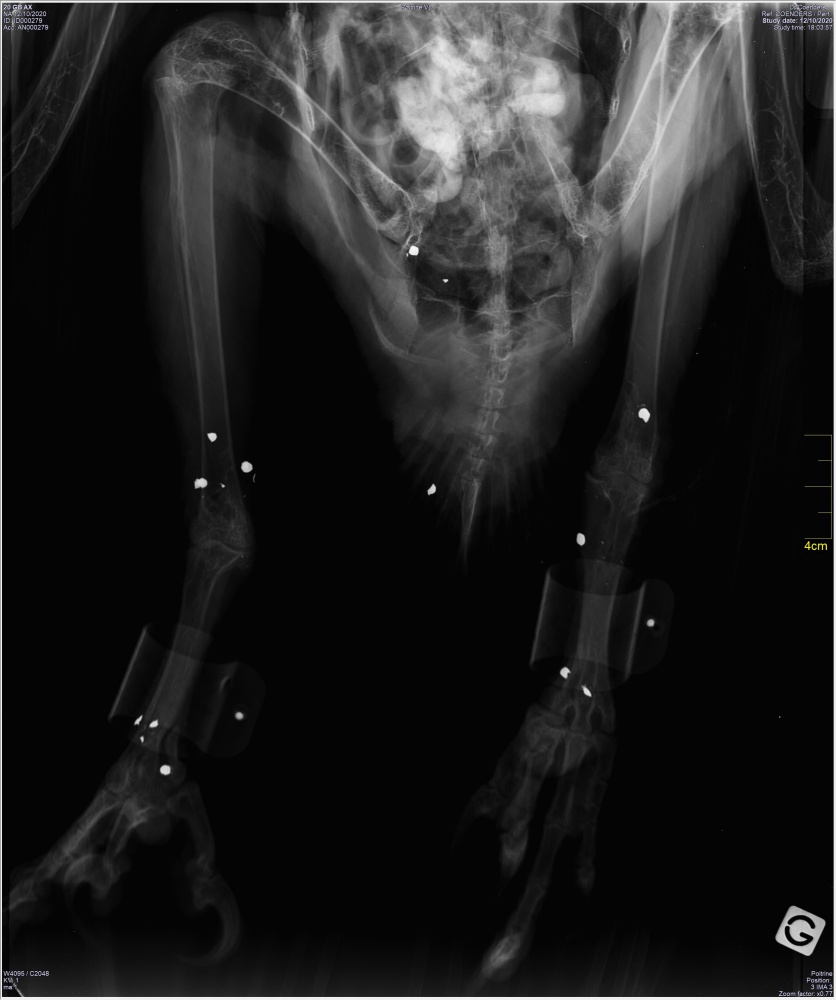

Suite à l’alerte lancée par le GPS de l’oiseau, Dolomie a été découvert mort au bout d’une piste forestière, sur le territoire d’une commune de Lozère, dans le Parc national des Cévennes. Le cadavre a été rapidement pris en charge en vue de la réalisation des protocoles d’autopsie et d’analyse. Dolomie présente une quinzaine de plombs de chasse à la radiographie. Ces plombs n’ont pas touché des organes internes, mais ont provoqué la chute de l’individu avec hémorragie sous-sternale, hémo péricarde et perforation de l’intestin, un petit bout d’os l’ayant percé pendant le choc. L’oiseau est donc décédé suite aux hémorragies internes.